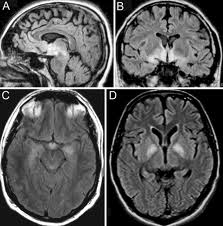

Encephalitis

Bij encephalitis, ook wel een ontsteking van hersenweef...